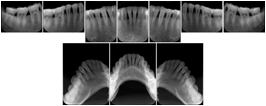

OO.1.4 Radiology

• A radiologist on his PACS assembles a screen layout of a stack of CT images of a current lung study, a secondary capture of a 3-D rendering of the CT, and a prior chest radiograph for the patient. He adjusts the window width / window level for the CT images, and zooms and annotates the radiograph to clearly indicate the tumor. He saves a Structured Display object representing that screen layout, including Grayscale Softcopy Presentation State objects for the CT WW/WL and the radiograph zoom and annotation. During the weekly radiology department conference, on an independent (non-PACS) workstation, he accesses the Structured Display object, and the display workstation automatically loads and places the images on the display, and presents them with the recorded WW/WL, zoom settings, and annotations.

• A mammographer reviews a screening exam on a mammo workstation. She wishes to discuss the exam with the patient's general practitioner, who does not have a mammo-specific workstation. She saves a structured display, with presentation states for each image that replicate the display rendered by the mammo workstation (scaling, horizontal and vertical alignment, view and laterality annotation, etc.).

Mammography Structured Display

Figure OO-7. Mammography Structured Display